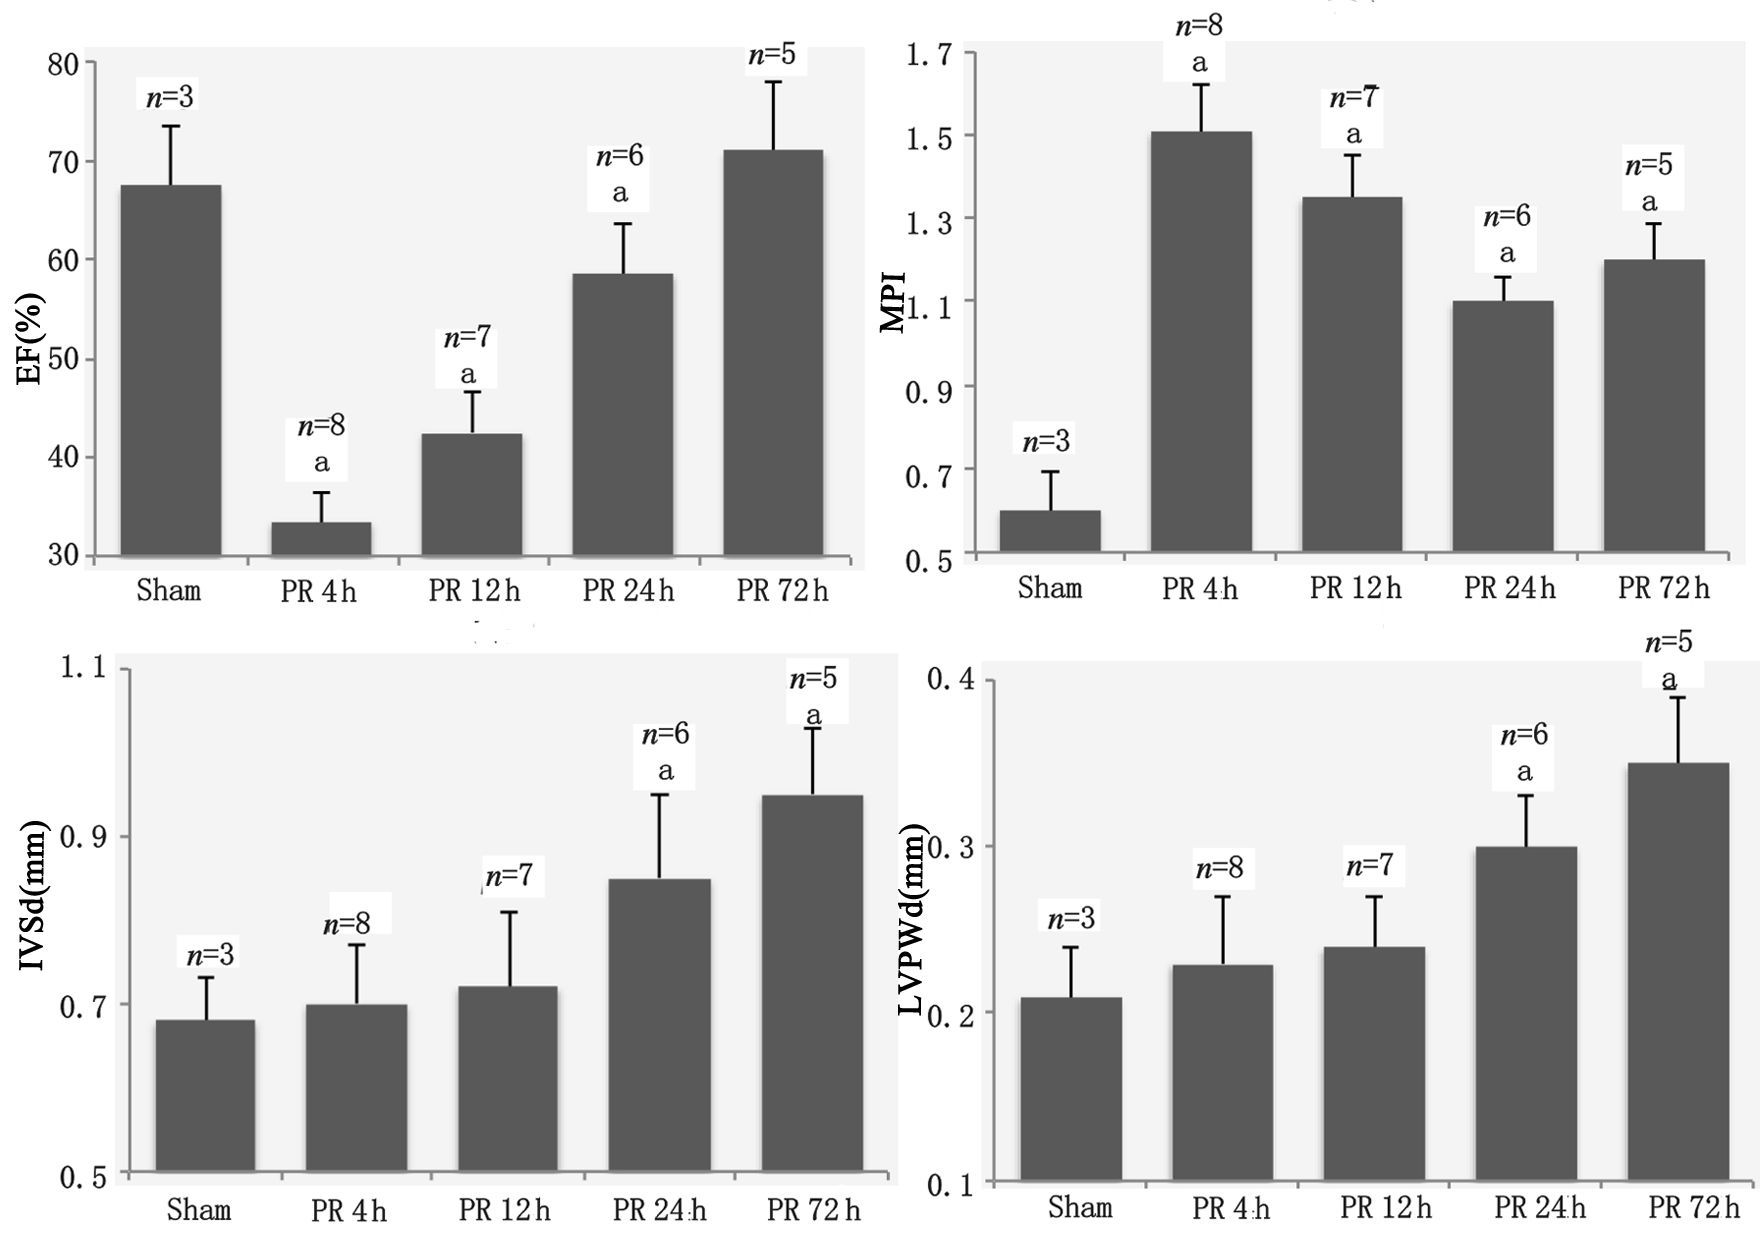

超声心动图结果示各组大鼠EF、MPI、IVSd和LVPWd等基线值的差异无统计学意义(均P>0.05) 。与Sham组比较,PR 4 h大鼠EF显著降低且MPI显著增高(均P<0.05) ,IVSd和LVPWd差异无统计学意义(均P>0.05) ;PR 12 h和24 h的EF值逐步恢复,但低于Sham组(P<0.05) ; PR 72 h与Sham组的EF差异无统计学意义(P>0.05) ;ROSC后各个时间点的MPI持续增高至PR 72 h(均P<0.05) ;PR 24 h和72 h的IVSd和LVPWd均高于Sham组(均P<0.05) ,见图 2和图 3。

| 计量资料采用均数±标准差(x±s)表示;与sham组比较,aP<0.05;PR为复苏后; EF为射血分数; MPI为心肌做功指数; IVSd为室间隔舒张末期厚度; LVPWd为左室后壁舒张末期厚度 图 3 超声心动图测量左心室结构和功能参数动态变化 Figure 3 Structural and functional parameters of left ventricle by echocardiography |